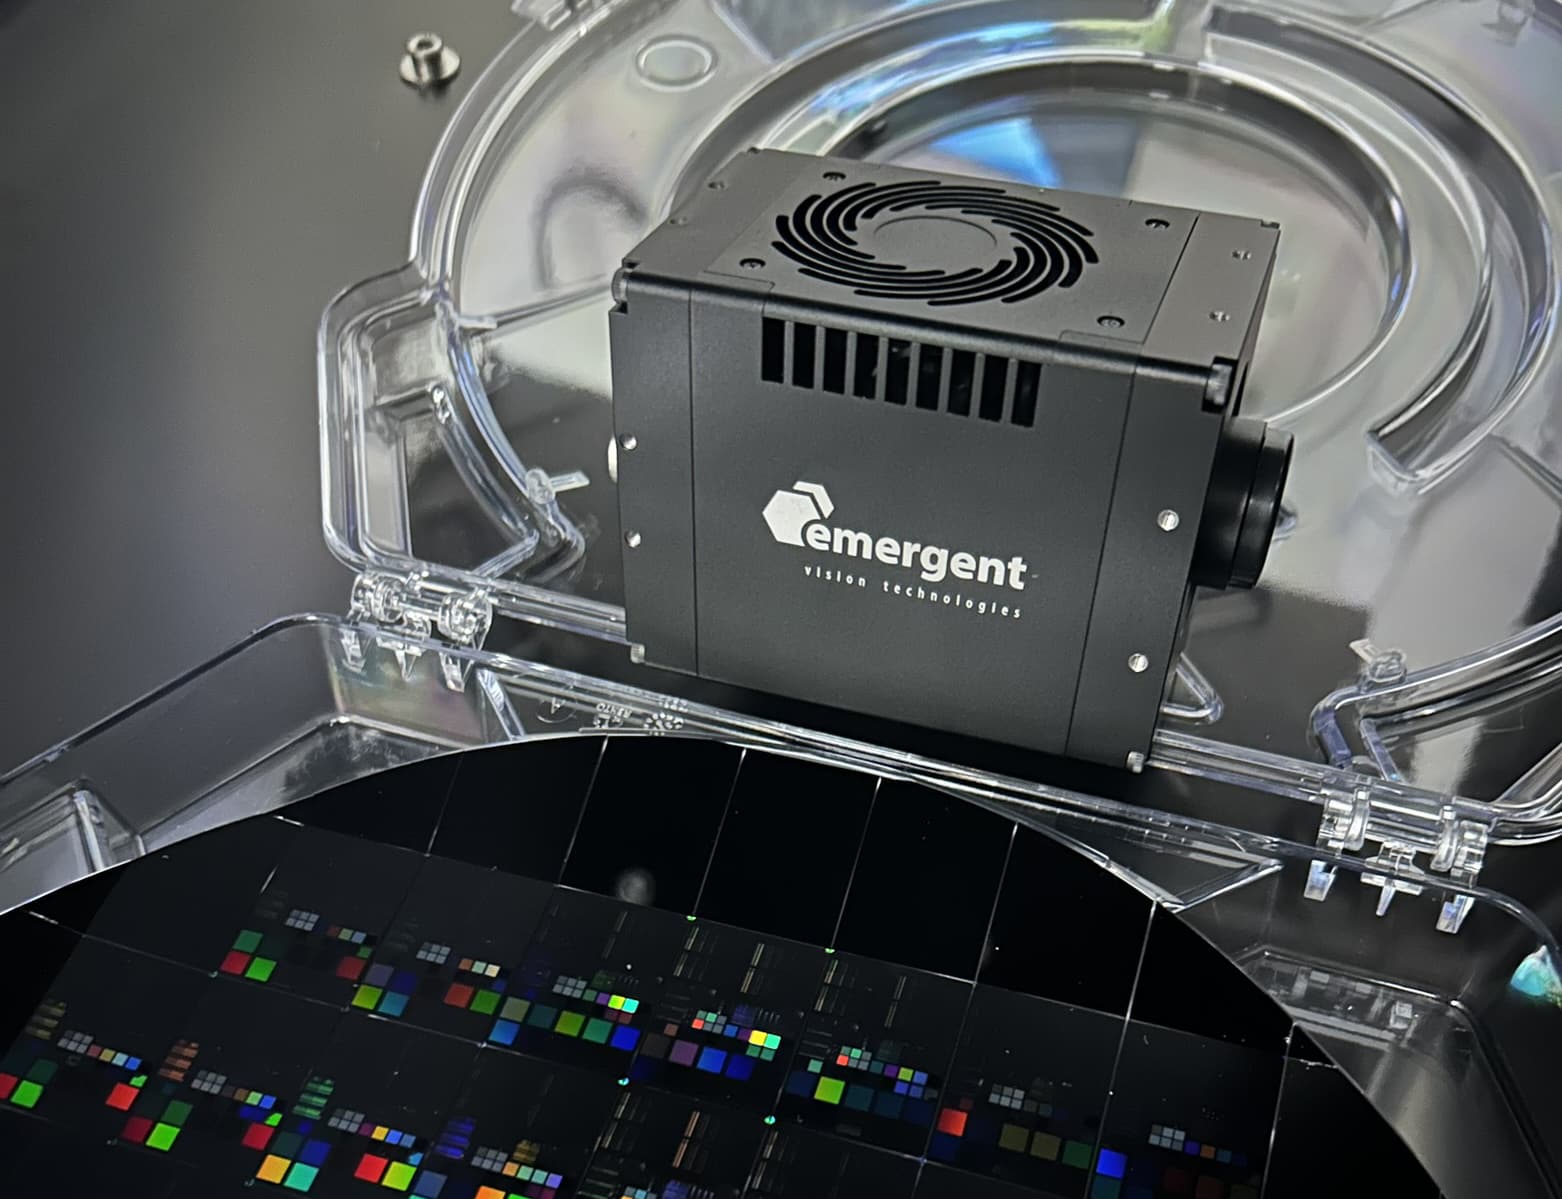

Daan Wolters adjusts the Emergent HZ-21000-G 100GigE high-speed camera that is fundamental to the lab’s work with phototransient holography.

In contrast, the VU Amsterdam team’s approach enhances conventional diagnostics by extracting richer, quantitative imaging data from tissue samples. Their phototransient holography technique, powered by the Emergent HZ-21000-G 100GigE high-speed camera, captures transient dynamics and photoinduced signals, enabling deeper insights into cellular composition and function.

The role of the 100GigE camera

The Matzlab team employs the Emergent HZ-21000-G 100GigE camera due to its exceptional speed and large field of view. This enables them to capture extensive sample areas—such as entire tissue slides—in rapid succession while switching light sources on and off.